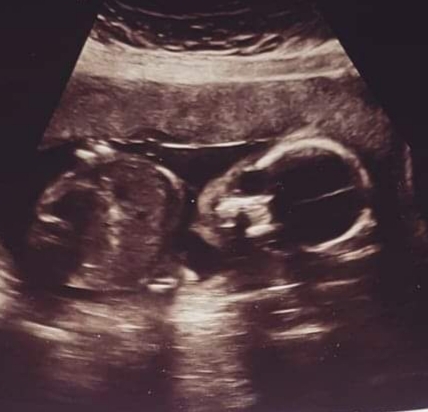

fluffyunicorns86 · 22/10/2019 14:42

Here is my scan pic. I am not sure what I think I am having. What you reckon baby could be

Lovely scan pic. I didn't realise there was such a thing as the nub and skull theory until reading this thread, so I'm interested to see what others think.

@mintbear well I thought the skull theory was that if it was more rounded it was a girl, and more angular for a boy! So I would've said definite girl for the skull theory but then the nub looks like it could be pointing up which suggests boy.... so in conclusion I'm not sure 😂 it's all just a bit of fun really.. everyone's interpretation of the scans is so different! Do you think you will find out? I am convinced I'm having another boy! All my random symptoms I have scream boy when I google them 🙈 Feel so lucky either way ❤️

@fluffyunicorns86 I would say boy, but it looks like the nub isn't visible so that's just going off the skull theory. My 12 week scan for my first was very similar and he is a gorgeous little boy!